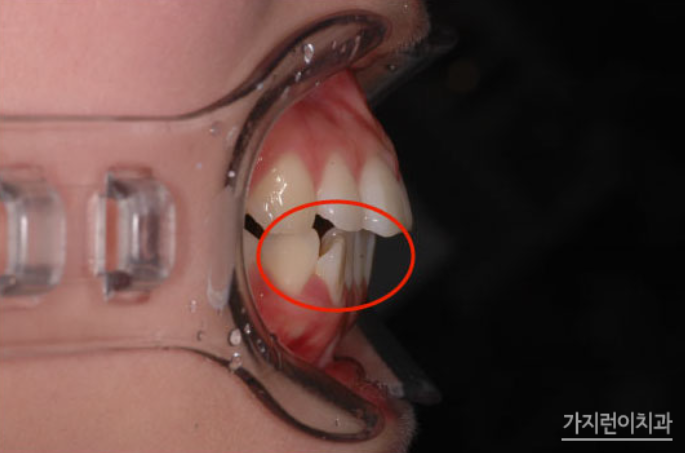

해당 환자분의 경우 잘 드러나 보이는 상악은 교정장치를 치아의 뒤에 부착하는 설측교정방식으로, 입술에 가려져 상대적으로 덜 부각되어 보이는 하악은 순측교정 방식으로 진행했습니다. 옥니를 교정하기 위해서는 치아를 이동시켜 다시 바깥 방향으로 각도를 조절해야 하기 때문에 충분한 힘을 받을 수 있도록 미니 스크류를 식립하여 교정용 고무줄을 연결했는데요. 상악 역시 앞으로 돌출되어 나온 부분을 뒤로 밀어 넣어야 하기 때문에 미니스크류를 식립하여 효과적으로 힘이 전달될 수 있도록 하였습니다.